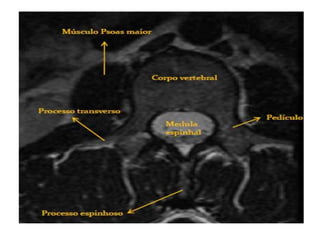

• A coluna vertebral é dividida em cinco

regiões: Cervical, Torácica, Lombar,

Sacro e Coccix.

C3 a C7: Corpo, arco neural posterior,

lâmina, pedículos, processos transversos

e espinhosos.